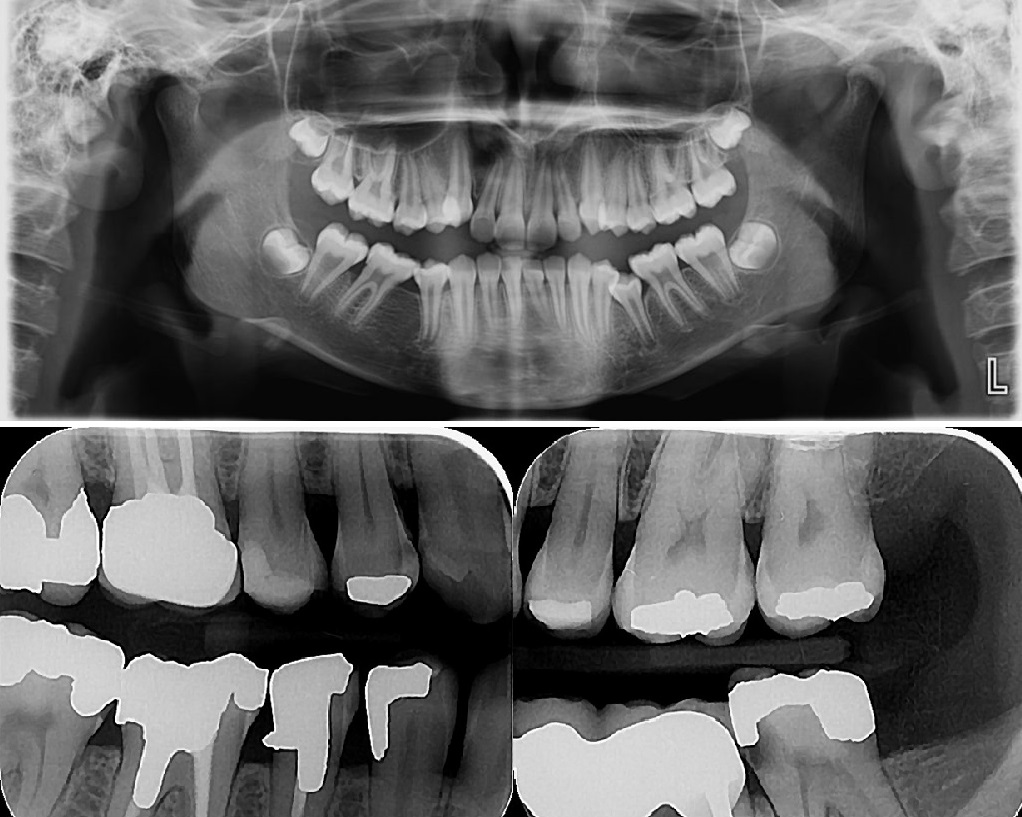

- رادیوگرافی پانورامیک

- رادیوگرافیهای داخل دهانی (پری اپیکال ،اکلوزال ،بایت وینگ)